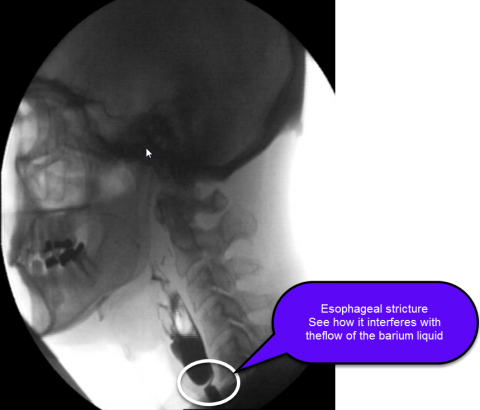

What is an esophageal stricture?

The esophagus is a muscular tube that connects the mouth to the stomach and is the conduit for food bolus to pass from the throat to the stomach. An esophageal stricture is a narrowing of the esophagus (see figure).

Specific testing is necessary to diagnose an esophageal stricture. An esophageal stricture can be diagnosed on a barium swallow study and/or upper endoscopy (EGD). In general, an upper endoscopy is needed to confirm the diagnosis and evaluate for the cause of the stricture.